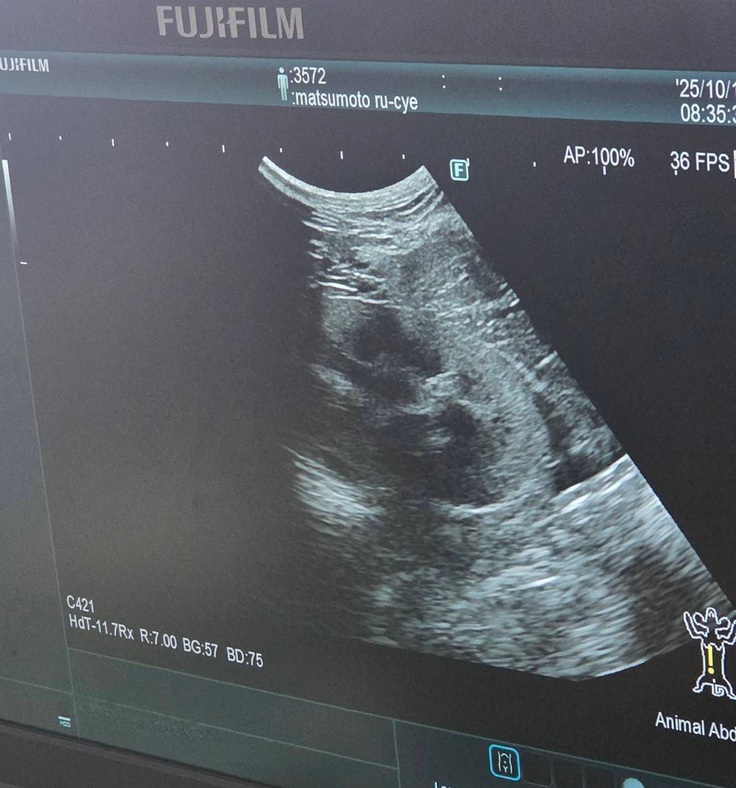

血液検査の写真は撮れなかったのですが、エコー検査では

↓腎臓転移なし

↓肝臓転移なし

↓膀胱転移なし

↓反対側の腎臓も転移なし

↓左目腫瘍なし

↓喉腫瘍なし

左目下頬の腫れは炎症によるものだったのではないかとの事でした。